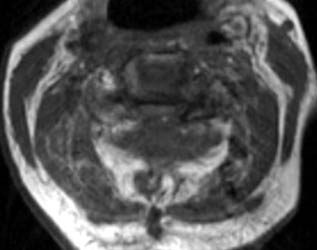

75 y.o. female with about a two-year history of continued gait abnormalities and decreased dexterity. On examination her strength was normal, however, she had bilateral Hoffmann signs as well as bilateral Babinski signs. Her strength was 5/5 but her gait was ataxic. Magnetic resonance imaging showed severe stenosis at C3, C5 and C6 levels. She underwent C3-C6 laminectomies.

Immediately post-operatively she did well, however, within 36 hours of the operation, she slipped and fell due to spilled milk on the floor . After that injury, the patient was neurologically intact. However, on postoperative day #2 for morning rounds, the patient was noted to be confused and weakened on the left side, both arm and leg, leg more than the arm. An immediate CAT scan of the brain and cervical spine was obtained. Immediate MRI was also obtained.

Non-enhanced sagittal T1 (A), sagittal T2 (B) and axial T1 images demonstrate a large fluid collection, predominantly low signal on T1, bright on T2 with a few areas of T1 hyperintesity mixed within. These constellation of findings are consistent with a post-operative epidural hematoma with blood products of various ages. There is severe severe spinal canal stenosis at C3-4, and very severe spinal canal stenosis at C4-5 and C5-6. The cord is markedly flattened in the anterior-posterior dimension, to approximately 2-3 mm secondary to mass effect from this fluid collection. There is abnormal T2 weighted hyperintensity within the substance of the cord at the C5-6 and C6-7 levels, consistent with some edema.